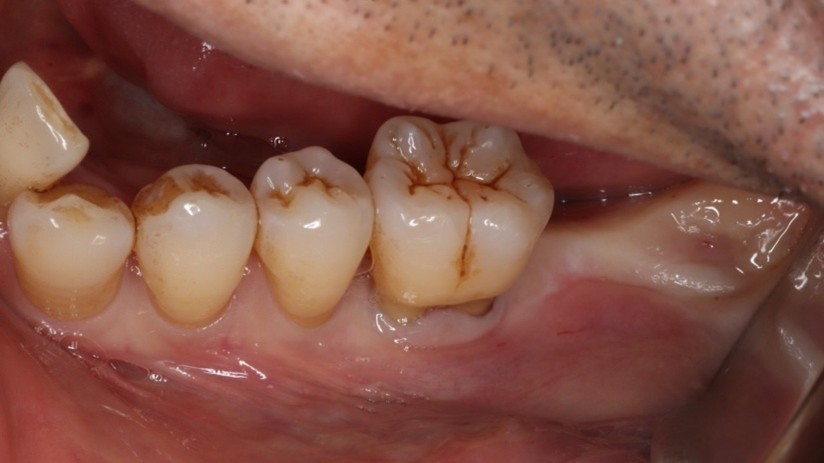

重度歯周病の患者様

もともと歯が揺れるということで来院された患者様で、検査をすると重度の歯周病でした。当院はインプラントに力を入れていますが「ご自身の歯」に勝るものはありません。外科治療も含めて徹底的な歯周病治療を行いました。